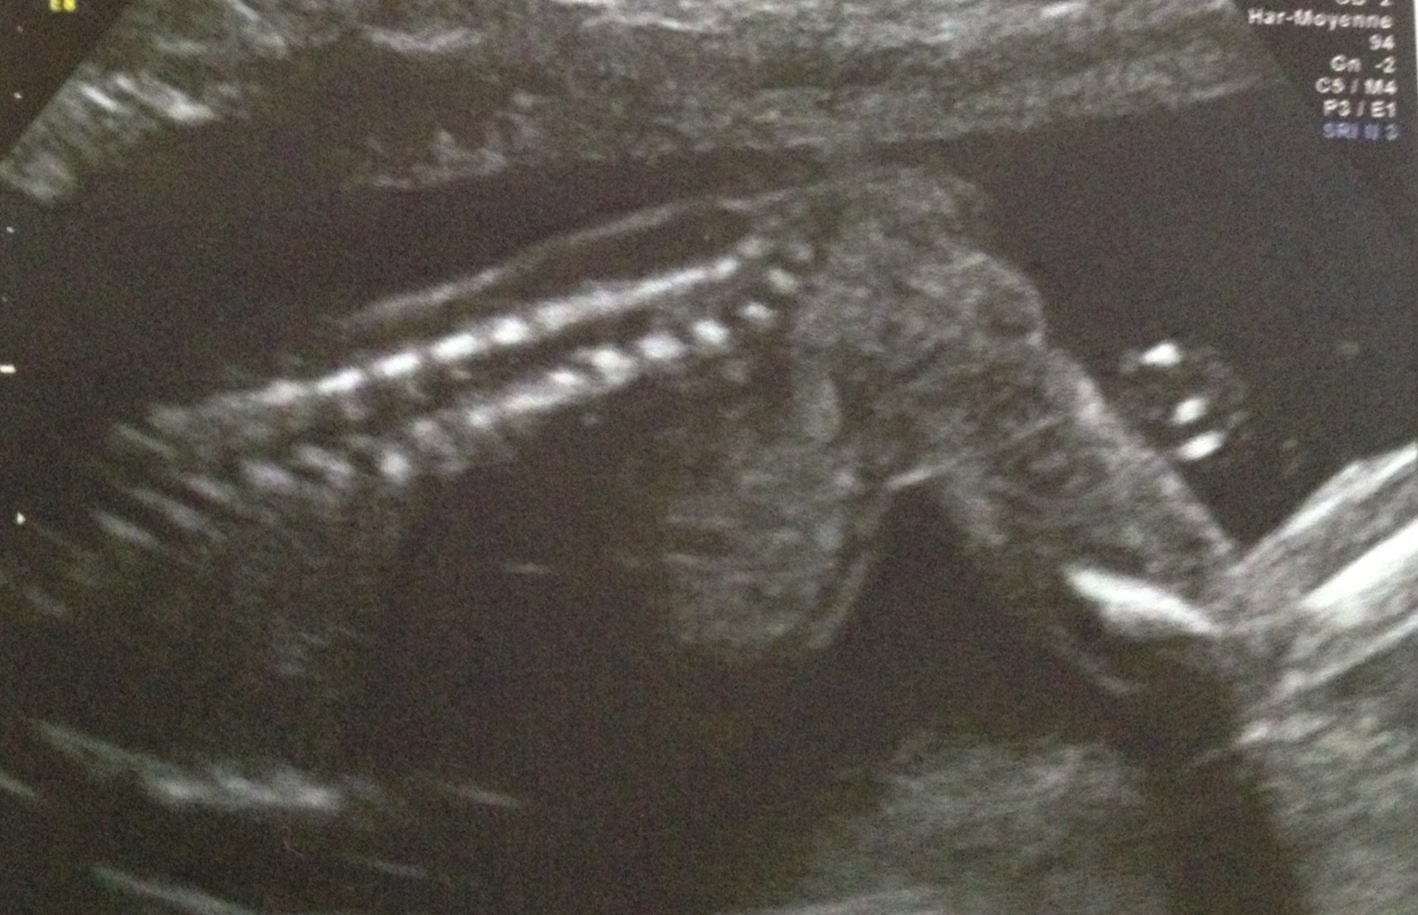

Mon fils n'aime pas les photos donc bon je pourrais pas vous montrer grand chose lol. Voilà son profil et son dos fesses et jambes lol. Mais a L'Echo on a trop bien vu sa bouche son nez des petit pieds ses petites mains fin génial ;)